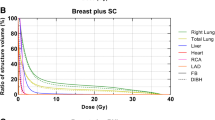

The average doses to the heart, LADCA and left lung in Gy following 3D-CRT and IMRT planning with the 3 different breathing maneuvers are shown in Fig. 2. In the FB, T-DIBH and A-DIBH modes, IMRT resulted in a lower mean dose to the heart, LADCA and left lung. Moreover, IMRT plans with A-DIBH achieved the lowest mean doses to the heart, LADCA and left lung.